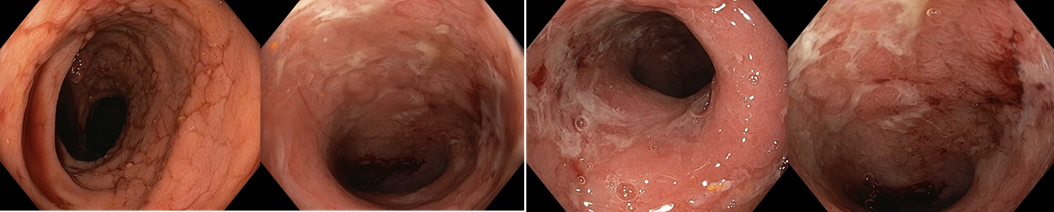

Koloskopie 2012/2: Endoskopický obraz Crohnovské pankolitidy, středně těžké až těžké (více je postižen P tračník), normální terminální ileum

2012/10 Endoskopický obraz mírné segmentální kolitidy charakteru Crohnovy choroby (rozsah postižení je 10-20 % tračníku) - podstatné zlepšení proti předchozímu nálezu, ke slizničnímu zhojení nedošlo

Koloskopie: Endoskopický obraz těžké segmentální kolitidy

2013/11 endoskopický obraz těžké pankolitidy charakteru Crohnovy choroby   - obraz cobble stones relativně je ušetřeno rektum, kde je ložiskově patrná   podslizniční cévní kresba

Koloskopie: Endoskopický kolitidy s ušetřením rekta, maximálním postižením v P tračníku – dle obrazové dokumentace zlepšení ve všech etážích tračníku   (i v P tračníku rozsah ulcerací snížen cca o 50%)